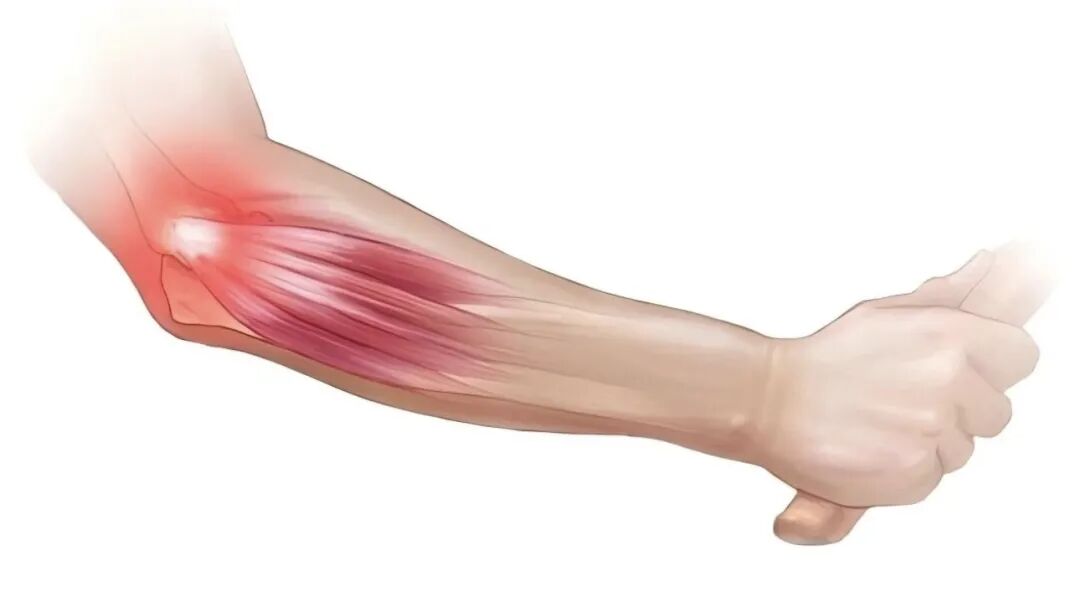

这位李阿姨是一位被“肘痛”肱骨外上髁炎困扰了3年的患者,3年间李阿姨接受了包括药物治疗、物理治疗和中医治疗,接受治疗期间疼痛缓解,停治疗后疼痛再次发作,严重影响正常生活。在朋友的介绍下李阿姨来到了康复医院创伤康复病区刘娜主任门诊,通过检查后刘娜主任诊断李阿姨患了“双侧肱骨外上髁炎”,详细询问了李阿姨的就诊史后,刘主任建议李阿姨接受PRP治疗,治疗3次后随诊1个月李阿姨疼痛未复发,为巩固疗效,刘娜主任建议李阿姨再治疗一次防止复发,才有了开头那一幕。

(3)软组织疾病/损伤:粘连性肩关节滑囊炎/肩周炎、肩袖损伤、肱骨外上髁炎、髌腱炎、跟腱炎、跖筋膜炎、腱鞘炎等;